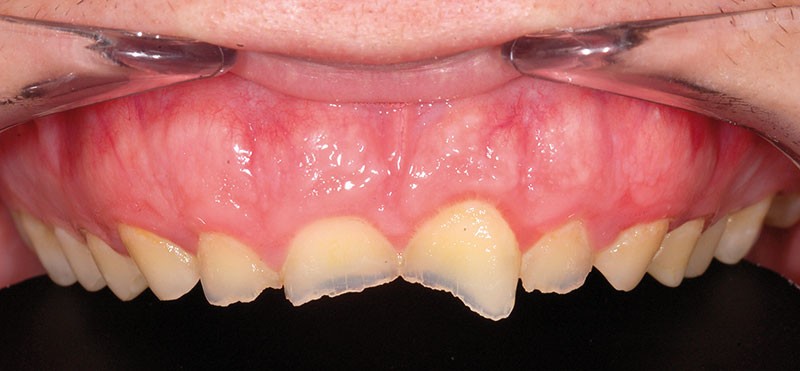

À l’examen clinique, les dents, principalement antérieures, présentent des pertes de substances importantes de classe V selon la classification ACE (Anterior Clinical Erosive Classification) de Vailati [1] (fig. 1 à 6).

Les examens complémentaires, dont un sondage parodontal, montrent l’absence de maladie parodontale (fig. 7).

Le parodonte marginal est de type 1 selon la classification de Maynard et Wilson [2]. On note également la présence d’une grande quantité de gencive attachée située apicalement par rapport aux lésions dentaires.